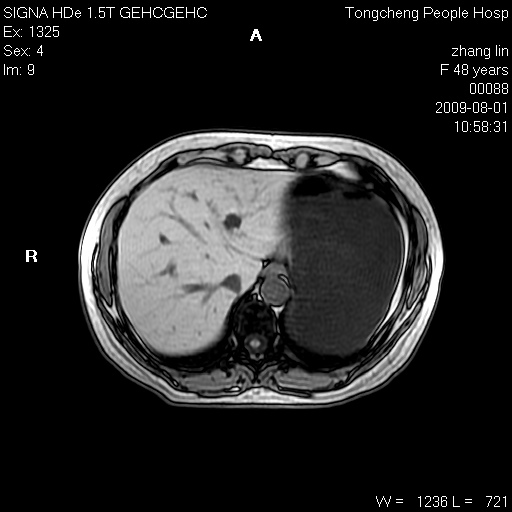

女,48岁。健康体检,彩超发现右肾占位性病变。平素健康。

临床诊断:右肾占位性病变,性质待定(囊肿?肿瘤?)。

上中腹部mr平扫+增强扫描,图像如下:

右肾上极见一类圆形病灶,t1wi呈等信号t2wi呈等高混杂信号,三期增强无强化,边界清---考虑囊肿出血。

同反相位均表现为等信号,病变无强化,考虑含蛋白的囊肿可能,弥散加权相或许有些帮助,

慢性胆囊炎